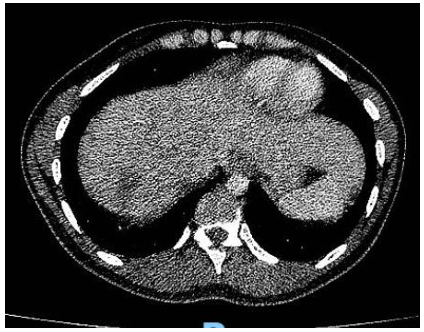

Debido a este hallazgo, con sospecha de enfermedad trofoblástica gestacional maligna se decide solicitar estudios de extensión TC tórax(Imagen 1), abdomen y pelvis(Imagen 2) en los cuales se evidencian múltiples lesiones focales en ambos campos pulmonares, destacándose por su tamaño, aquella ubicada en región anterior del campo pulmonar derecho, comprometiendo lóbulo medio y lóbulo superior, de 25mm. Sugieren valorar secundarismo. El hígado presenta múltiples lesiones focales heterogéneas, con realce con el contraste endovenoso, la mayor a nivel del segmento Vll, de 60mm, vinculables a secundarismo en primer término. Bazo de tamaño conservado, con lesión de semejantes características a las descritas en hígado, de 42mm, asimismo sugerente de secundarismo. Útero ausente en relación a los cambios descritos. Se observan aparentes engrosamientos nodulares a nivel del lecho quirúrgico, que realzan tras la administración de contraste EV y sugieren la presencia de implantes.

Imagen 2. TC abdomen (corte a nivel superior) al diagnóstico